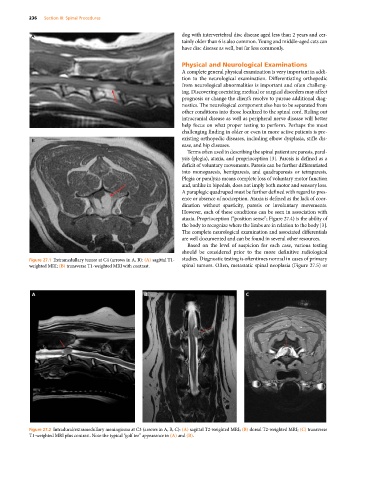

Figure 27.1 Extramedullary tumor at C4 (arrows in A, B): (A) sagittal T1‐ studies. Diagnostic testing is oftentimes normal in cases of primary

weighted MRI; (B) transverse T1‐weighted MRI with contrast. spinal tumors. Often, metastatic spinal neoplasia (Figure 27.5) or

A B C

Figure 27.2 Intradural/extramedullary meningioma at C3 (arrows in A, B, C): (A) sagittal T2‐weighted MRI; (B) dorsal T2‐weighted MRI; (C) transverse

T1‐weighted MRI plus contrast. Note the typical “golf tee” appearance in (A) and (B).